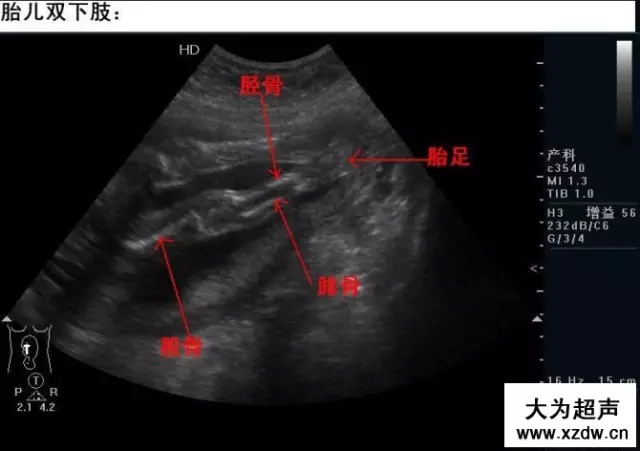

產(chǎn)科超聲正常圖片